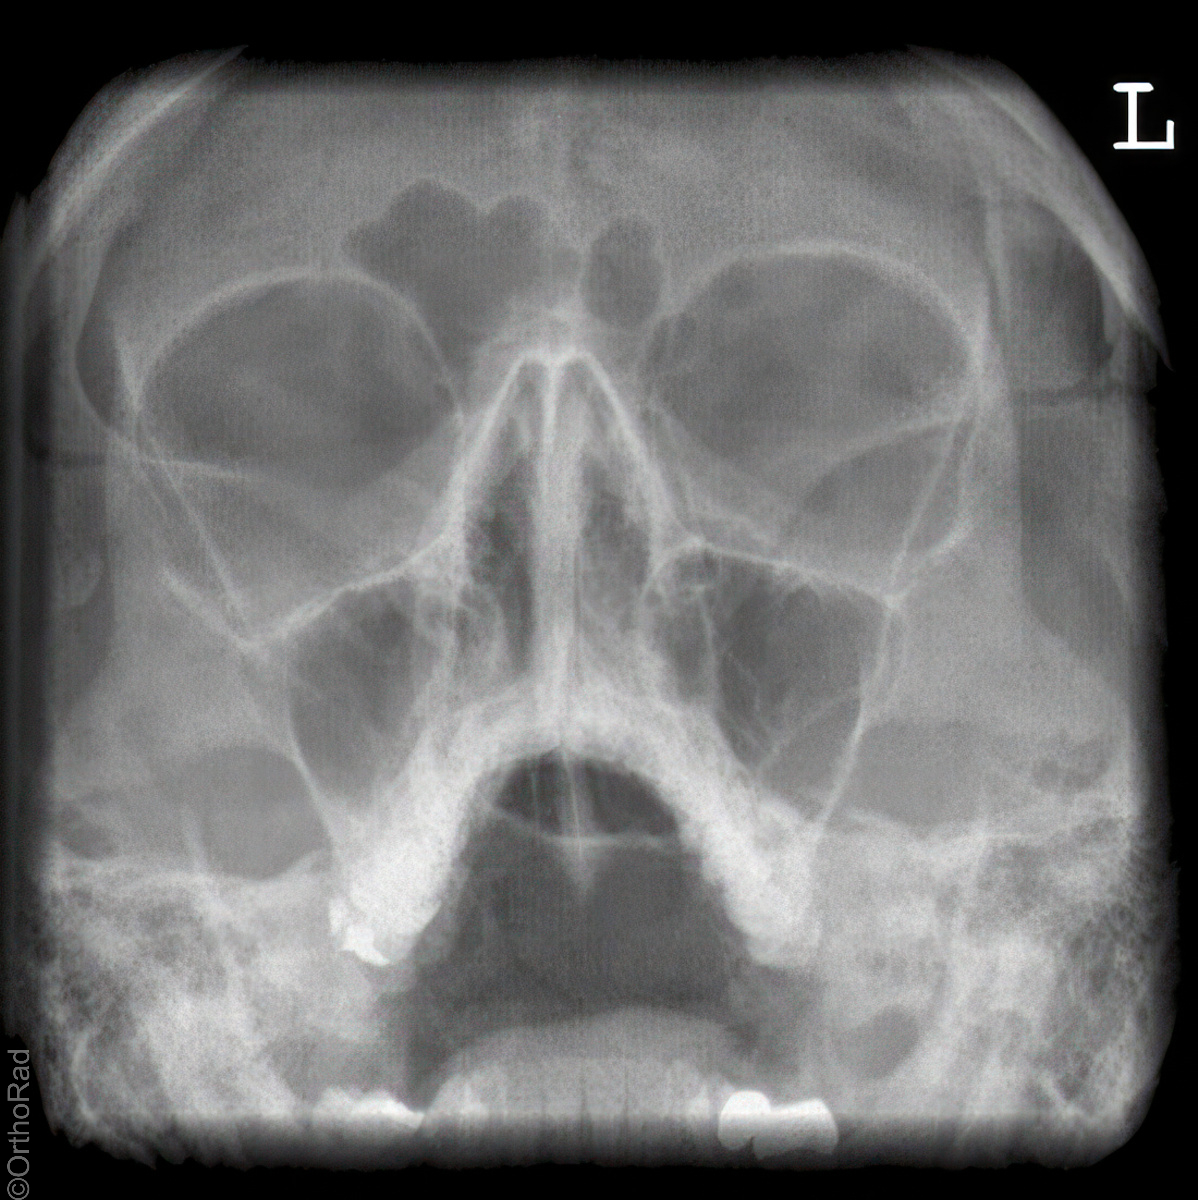

Nasennebenhöhlen (NNH)

Technik

• FDA: 1,15 m

• Ausgangsformat: Detektor oder 18/24 hoch

• mit Raster

Indikation

Sinusitis, Z. n. Osteosynthese

Lagerung

sitzend mit Gesicht zum Stativ

Hände festhaltend am Stativ

Rücken gerade

Mund weit geöffnet

Kinn liegt auf, Nase schwebt

Kopf anheben bis obere Zahnreihe und 1 QF über Ohr-Rand eine Linie bilden

Zentralstrahl

Querstrahl: 1 QF über oberen Ohrrand & Oberlippe

Längsstrahl: Medianebene

Einblendung

lateral auf Augenwinkel, cranial: auf Haaransatz

Anmerkung

Besonders auf symmetrische Lagerung achten. Im Sitzen ist evtl. Flüssigkeitsspiegel gut beurteilbar.

Qualitätskriterien

Symmetrische Darstellung des Gesichtsschädels: seitengleiche Distanz zwischen lateralem Rand der Augenhöhle und äußerer Schädelkontur. Die Pyramidenoberkanten kommen unmittelbar unterhalb des Kieferhöhlenbodens zum Liegen, also in die obere Zahnreihe, sodass die Kieferhöhlen überlagerungsfrei zur Darstellung kommen.